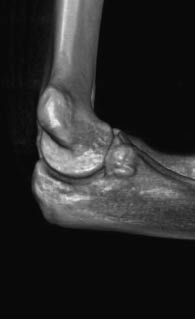

Radiography and computed tomography were performed (Figures 1–3). An aseptic necrosis was detected in the region of the tubercle of the coronary process in the fragmentation stage.

Fig. 1. Radiograph of the left elbow joint. Fragmentation stage of the region of the coronoid process tubercle